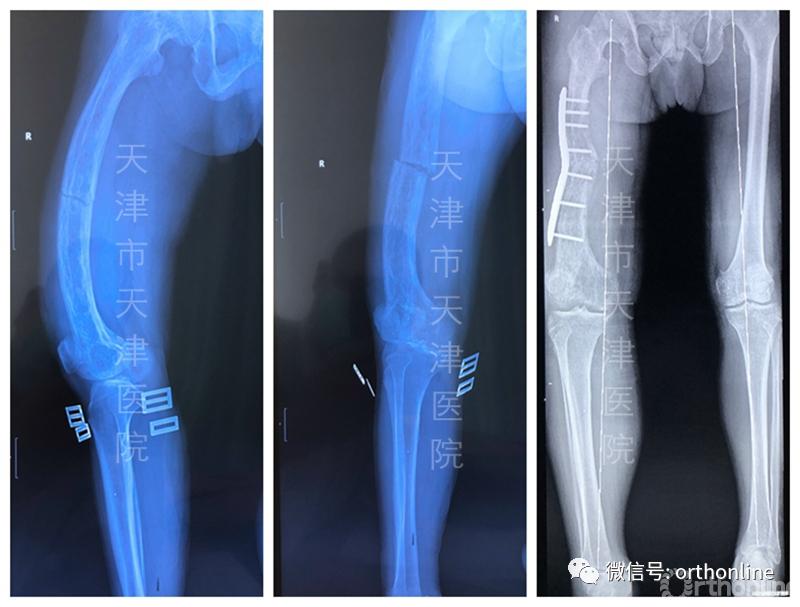

6月初,一位60多岁的paget病(畸形性骨炎)患者发生病理性骨折,患者股骨畸形且粗大,骨皮质变薄,骨小梁稀疏,患肢短缩近6厘米。通常,下肢骨折采用髓内钉固定治疗,但是并没有适合此例患者如此弯曲股骨的髓内钉,那么如何选择治疗方案,是进行外固定治疗还是保守的骨牵引治疗呢?

针对这一问题,马信龙教授团队通过进行低剂量CT分析,复位观察患肢骨折部位原来的畸形形态,决定通过畸形矫正的原则一并解决其骨折和畸形问题。

为此,他们在术前经过数字技术反复模拟设计个性化手术方案,为了对骨折端精准截骨,专门设计了两个个性化截骨导板,分别在骨折端远端和近端完成截骨,然后进行整体复位和个性化钢板固定。在治疗骨折的同时矫正了畸形,术后患肢仅比健肢短1厘米,达到了很好的治疗效果,减轻了患者的痛苦。此类手术已经陆续开展了200余例,均达到了良好的手术效果。

一例Paget's病合并病理性骨折患者术前术后影像片

这种手术对医生是巨大的挑战,但对患者而言是一举两得的好结局。目前,天津医院版个性化手术方案不仅在本院临床应用,还为国内其他医院进行手术方案规划,设计截骨导板和导向器,造福更多患者。